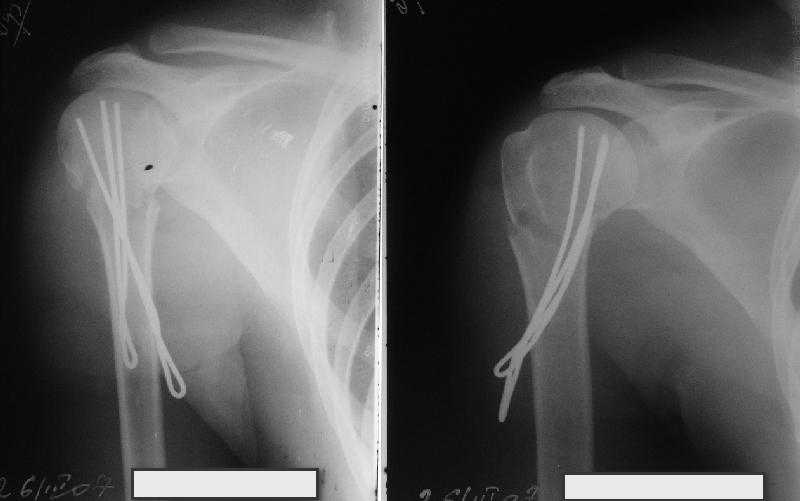

Сделали напряженными спицами по методике А.Ф.Лазарева со товарищи Репозиция сделана спицевым дистрактором, проксимальная спица была проведена в полскости деформации перпендикулярно оси наклонившейся головки. Получилось все довольно легко. Спицы малость покороче можно было сделать, ну да удалять потом легче будет.

Картинка в приложении.

Очень даже неплохо получилось. Молодцы! Лучше чем на 3D "репозиции".

Все заняло 1 час. Собственно введение фиксаторов - минут 20.

Оставили в косынке, сразу разрешены маятникообразные движения в плечевом суставе. Дальше по ходу расскажу.